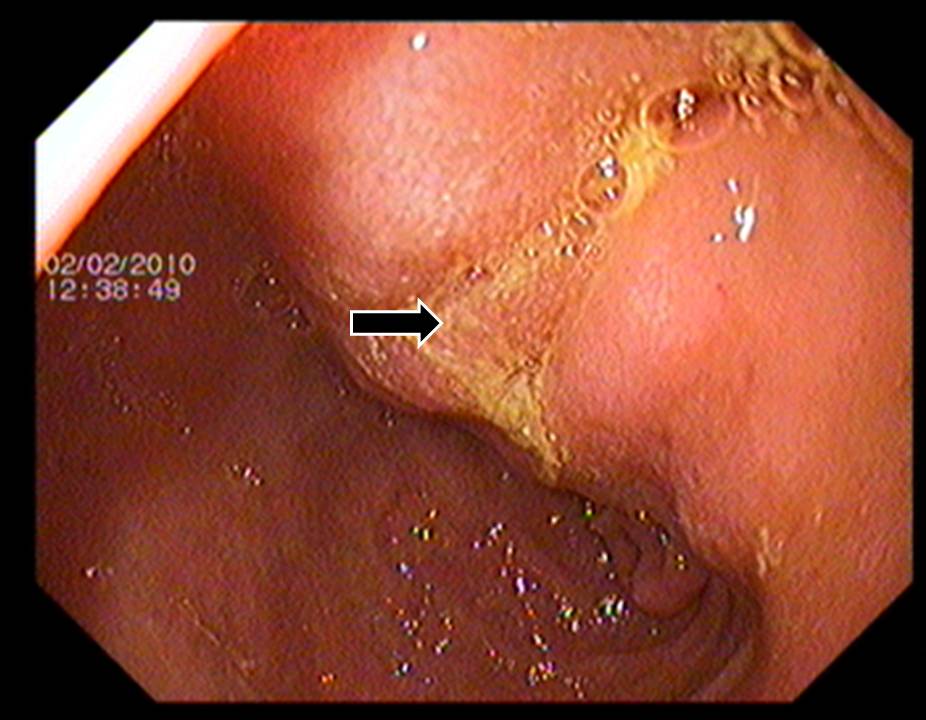

Context Diffuse large B-cell lymphoma is the commonest form of non-Hodgkin lymphoma. Gastro-intestinal tract and bone marrow are common extra-nodal sites of lymphomatous involvement. Case report A 54-year-old woman presented with acute onset epigastric pain. On evaluation, raised serum amylase and radiological features of acute pancreatitis were detected. Gastroscopy revealed thickened folds in distal stomach, which on histopathology revealed large B-cell lymphoma. Subsequently, the patient developed extra-hepatic biliary obstruction due to peripancreatic lymph nodal mass that was relieved with plastic biliary stenting. Subsequent chemotherapy regime directed against lymphoma led to resolution of lymphoma. Conclusion In this patient , pancreatitis was the initial presentation of primary gastric lymphoma, which has not been commonly reported and therefore should be considered in the etiological workup.

Image: Thickened gastric folds in distal body.

Thickened gastric folds in distal body